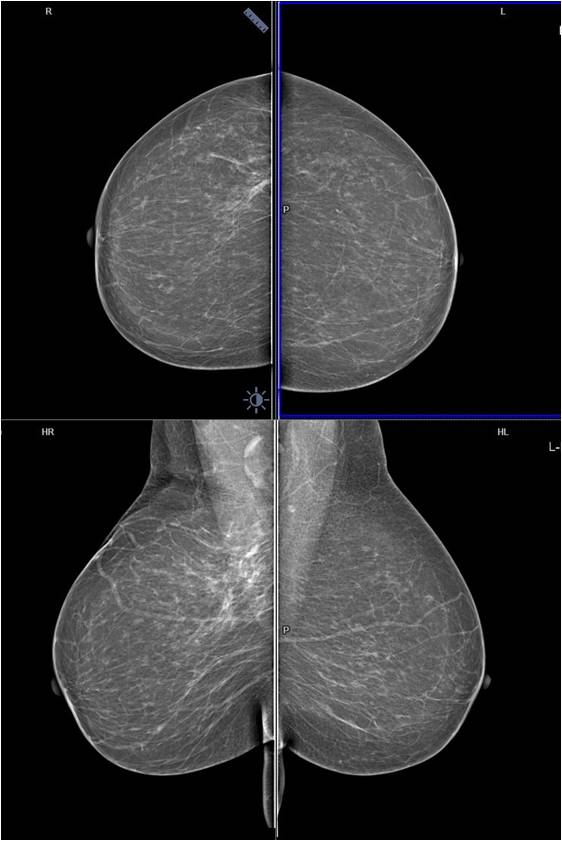

A 45-year-old asymptomatic woman with no family history of breast canc...

Read More